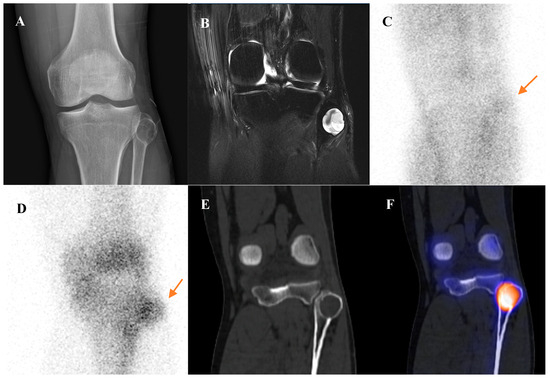

Current Position of Nuclear Medicine Imaging in Primary Bone Tumors

Primary bone tumors encompass a heterogeneous spectrum ranging from benign entities to highly aggressive sarcomas. This review aims to summarize the current role and future perspectives of nuclear medicine in the diagnosis, staging, and management of primary bone tumors. Accurate diagnosis and staging [...] Read more.

Primary bone tumors encompass a heterogeneous spectrum ranging from benign entities to highly aggressive sarcomas. This review aims to summarize the current role and future perspectives of nuclear medicine in the diagnosis, staging, and management of primary bone tumors. Accurate diagnosis and staging are critical yet challenging due to histologic heterogeneity and overlapping imaging features. While radiographs, computed tomography (CT), and magnetic resonance imaging (MRI) remain essential, nuclear medicine provides a complementary functional perspective by assessing bone turnover, vascularity, and glucose metabolism. Bone scintigraphy is highly sensitive for skeletal lesions and useful for detecting skip lesions or multifocal disease, although its specificity is limited. Hybrid single-photon emission computed tomography (SPECT)/CT enhances diagnostic confidence through precise anatomic localization and quantitation. [18F]fluorodeoxyglucose ([18F]FDG) positron emission tomography (PET)/CT, by directly visualizing tumor metabolism, has become a cornerstone in osteosarcoma and Ewing sarcoma management, demonstrating superiority over bone scintigraphy for detecting skeletal metastases. In chondrosarcoma, [18F]FDG uptake correlates with histologic grade, although overlap with benign cartilage tumors complicates interpretation. Future directions include the integration of quantitative SPECT, artificial intelligence, and novel tracers such as [18F]sodium fluoride and [68Ga]Ga-fibroblast activation protein inhibitor (FAPI). Collectively, nuclear medicine imaging is becoming a key element in musculoskeletal oncology, offering unique biological insights that complement anatomic imaging and contribute to improved patient management. Full article